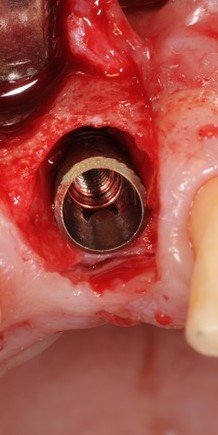

В далеком 1986 году американский профессор V. Morgan разработал концепцию субкрестальных коротких имплантов с фрикционной платформой. Последнее означает, что ортопедический интерфейс не имеет каких-либо антиротационных элементов (шестигранника и т. д.), а фиксация супраструктуры, коронки или абатмента, происходит путём «заклинивания»:

В этом есть, безусловно, революционность имплантов Bicon, их отличие от других современных имплантационных систем, в этом их главное преимущество и главный недостаток.